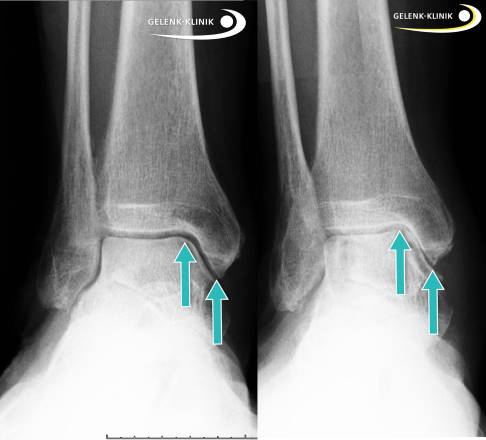

Der Grad des Knorpelschadens lässt sich mit weiteren diagnostischen Maßnahmen feststellen. Moderne Methoden sichern die Diagnose, um zum einen den Verlauf bei einer nichtoperativen Behandlung kontrollieren zu können und zum anderen vor einer Operation das genaue Vorgehen festzulegen.

Dafür erfolgen zur Stellungskontrolle der einzelne Knochen des Sprunggelenks Röntgenaufnahmen unter Belastung. Gleichzeitig kann eine Knochenschichtung im Rahmen einer DVT (digitale Volumentomographie) erstellt werden. Auch die klinische Untersuchung zur Klärung der Bandstabilität des Sprunggelenkes ist unbedingt notwendig.

Die Kernspintomographie (MRT) ist wenig geeignet, um einen Knorpelschaden am Sprungbein direkt darzustellen. Dafür zeigt das MRT gegebenenfalls ein Knochenödem oder Knochenzysten als Zeichen der Knochenreaktion.